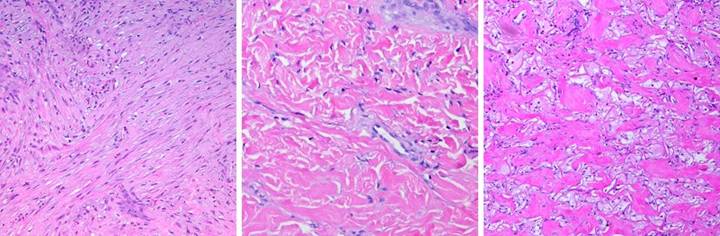

Case Study 11,  Location, trunk.   A 51 year old woman, with dialysis dependent renal disease and tertiary hyperparathyroidism, developed multifocal necrosis and ulceration of the trunk.  (Figure 11a)  The history, pattern of involvement, and the debilitating ischemic pain were all typical of systemic calcinosis (calciphylaxis).  The diagnosis is easily made by clinical features, but histology of debrided material confirms it.  Medial arteriosclerosis of all small order arteries and arterioles is characteristic, often accompanied by microthrombosis.  (Figures 11b,c)  The patient had numerous infarcted lesions on the trunk.  The right breast and right flank (lower abdomen) are shown.  This condition is refractory to usual topical and surgical care.  Progressive necrosis is common, and attempts to debride can cause more necrosis (pathergy).  Managed by good topical care alone, many months may be required for closure.  Skin grafts and customary repairs are likely to fail or cause more problems.  (Figures 11d,e)  All necrotic areas were excised and closed with Integra.  Pain and progressive ulceration immediately ceased.  All areas healed quickly, seen here 3 months after excision and Integra.  This is the paradigm Integra reconstruction, complete success without delays.  Integra’s ability to close and control the wound without donor sites nor risk to the patient is ideally suited to this diagnosis.

Figure 11  a (left), b (top middle), c (top right), d (bottom middle), e (bottom right)